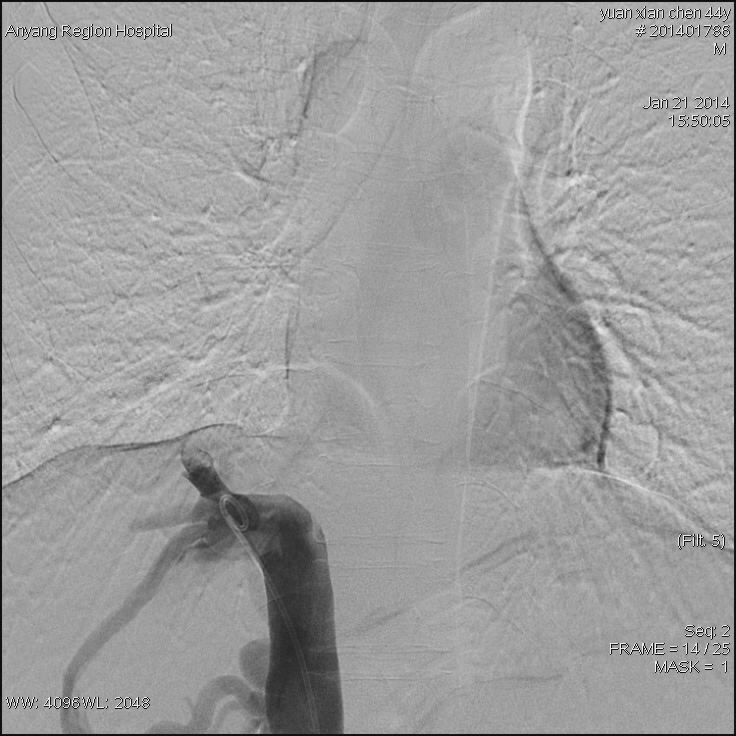

接受治疗的是一位44岁男性患者,该患者常年消化不良,身体异常瘦弱,肝脾肿大,双下肢静脉曲张合并腹壁静脉曲张,经核磁影像检查,诊断为布加综合征,考虑为下腔静脉肝后段膜性闭塞病变。我院介入科主任高毅组织科室医务人员认真研究患者病情,并详细制定出多种介入开通方案。1月21日,为患者进行了介入治疗。手术中,经穿刺股静脉与颈内静脉双向造影后,进一步明确了该患者为膜性闭塞。采用破膜针开通闭塞段,引入加硬导丝,交换引入较大球囊扩张后,患者下腔静脉瞬间畅通,下腔静脉压力明显下降,下肢静脉及腹壁静脉曲张立即消失,六小时后患者即下床活动,困扰患者多年的头晕等症状也随之消失。